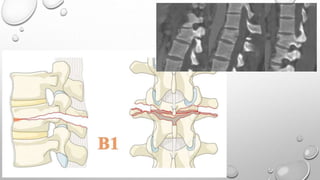

Tipo B

Describe falla del complejo ligamentario posterior

o el ligamento longitudinal anterior.

B1: Disrupción de la banda de tensión trans-osea

/ Fractura oportunista

B2: Disrupción de la banda de tensión posterior

B3: Hiperextensión